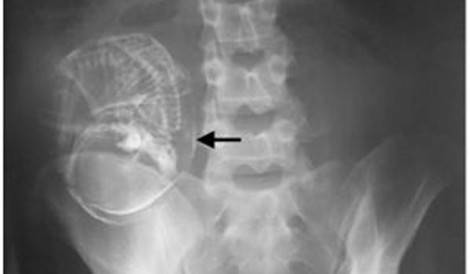

Immaginatevi la sorpresa una volta ritirato il referto delle lastre, quando il medico dice alla donna ‘complimenti, lei è incinta’. In realtà il feto, ormai calcificato nel corpo della donna, era li da ben 40 anni. Una gravidanza di cui evidentemente la donna a suo tempo non era a conoscenza, la morte inaspettata del feto e l’impossibilità del suo fisico dell’espulsione di quest’ultimo a causa della sua grandezza erano le cause dei continui disturbi dell’ignara signora. Un’operazione ha finalmente permesso di dare alla ‘luce’ questo feto di ben 40anni di età. Da non credere!